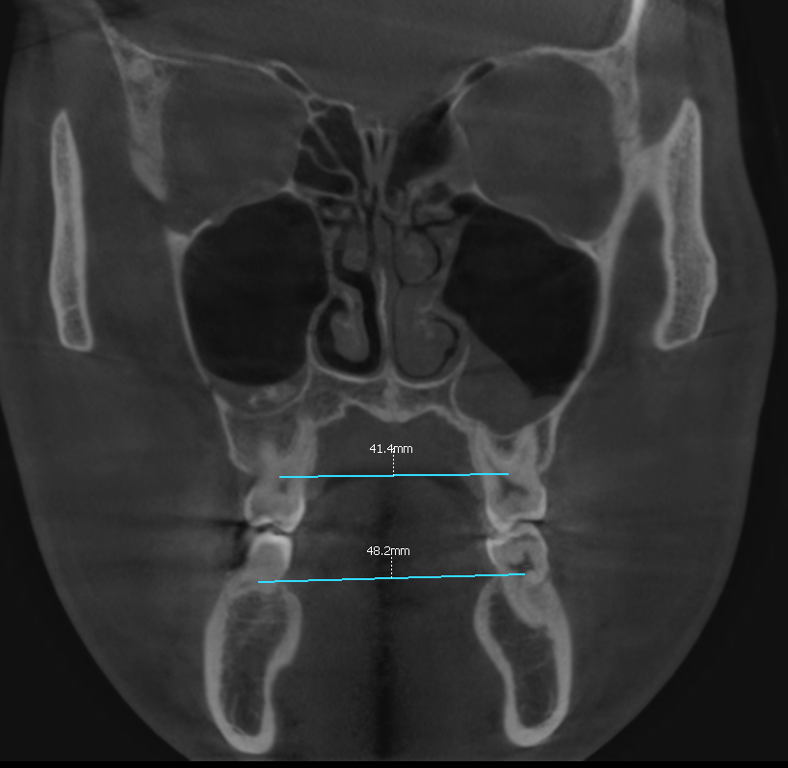

위아래 어금니 간 폭경의 비율이

부조화를 보인 것을 볼 수 있습니다.

더불어, 왼쪽 비강의 협착과

상악동 염증 소견이 보입니다.